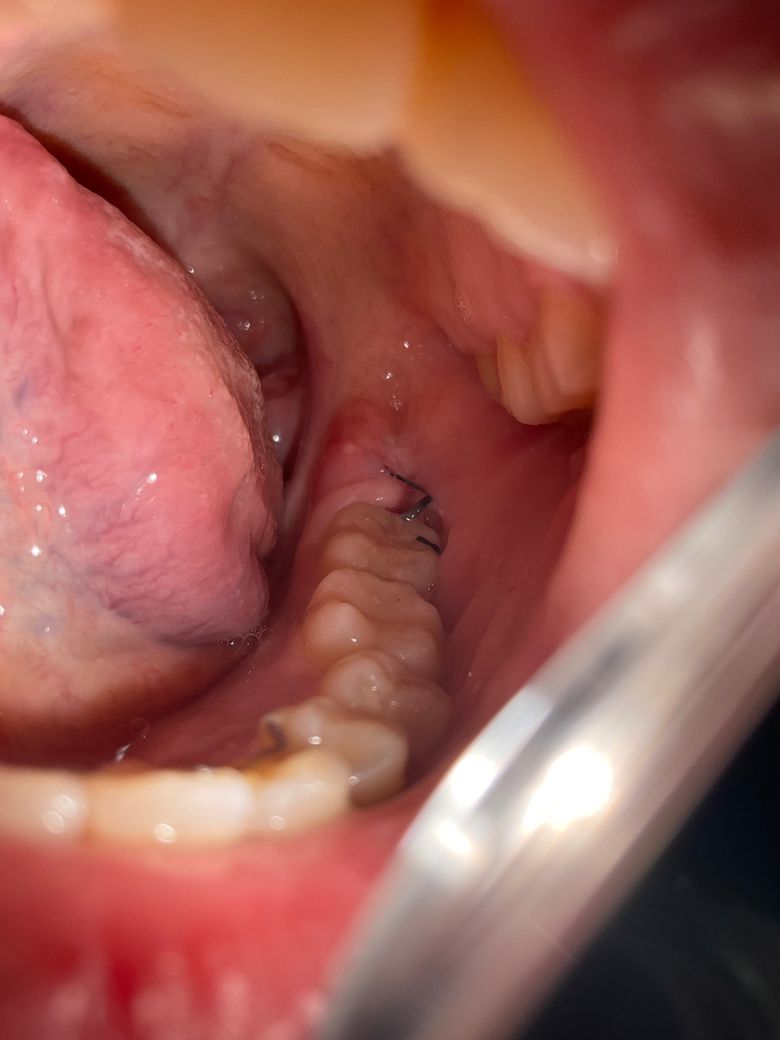

두번째 사진에서 초록색 표시부위쪽에 하얀 무언가가 있는데 아프지는 않은데 문제가 되려나요??

• 2번 째 사진

사진상으로는 염증이나 기타 문제를 의심할만 한 것은 보이지 않으니 지금처럼 관리해주시면 됩니다.

사진상으로 보면 사랑니 발치를 한곳이 잘 아물고 잇는거 같습니다. 큰 문제가 잇는건 아니니 자극만 가지 않도록 해주세요.

사진으로만 봤을 경우에는 크게 문제가 되지 않을 것으로 생각됩니다. 하지만 해당 부위에 불편하거나 붓는 느낌이 있다면 치과에서 진료를 받아보는 것이 좋습니다.

두번째 사진에서 초록색 표시부위쪽에 하얀 무언가가 있는데 아프지는 않은데 문제가 되려나요?? -> 괜찮습니다